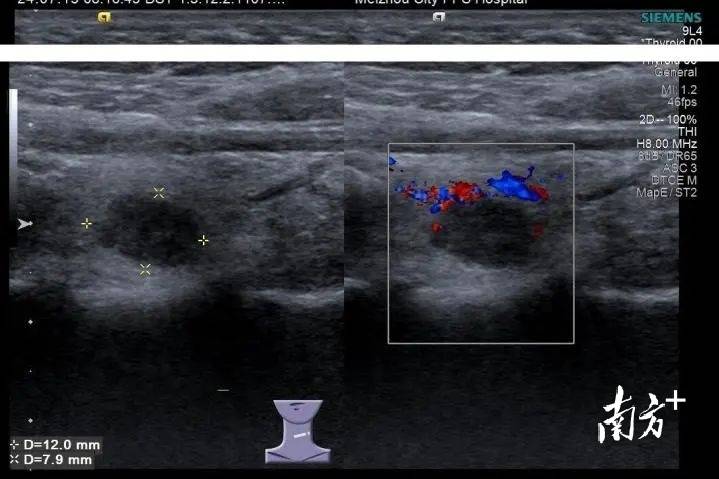

小罗是一名在校女大学生,家住在吉林省白城市,近期体检中发现甲状腺有个结节,彩超提示为C-TIRADS 4A类,存在恶性病变风险。看到检查报告时,小罗很害怕,“存...